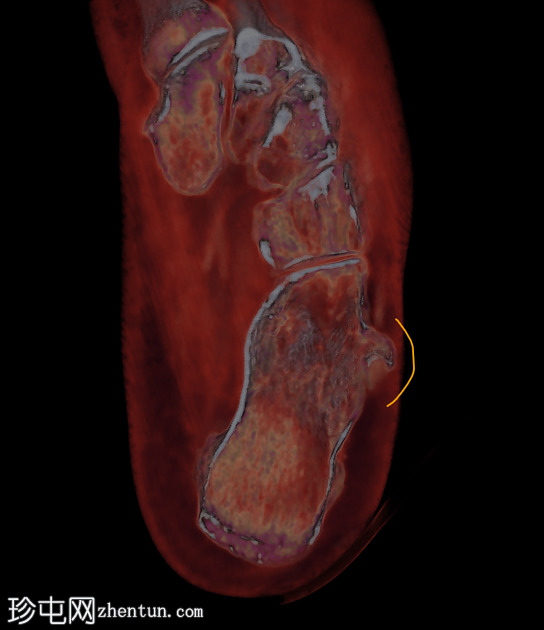

临床表现

跟骨外侧

疼痛

。

患者资料

年龄:65岁

性别:女

跟骨轴位CT

腓骨结节解剖图(带注释)

病例讨论